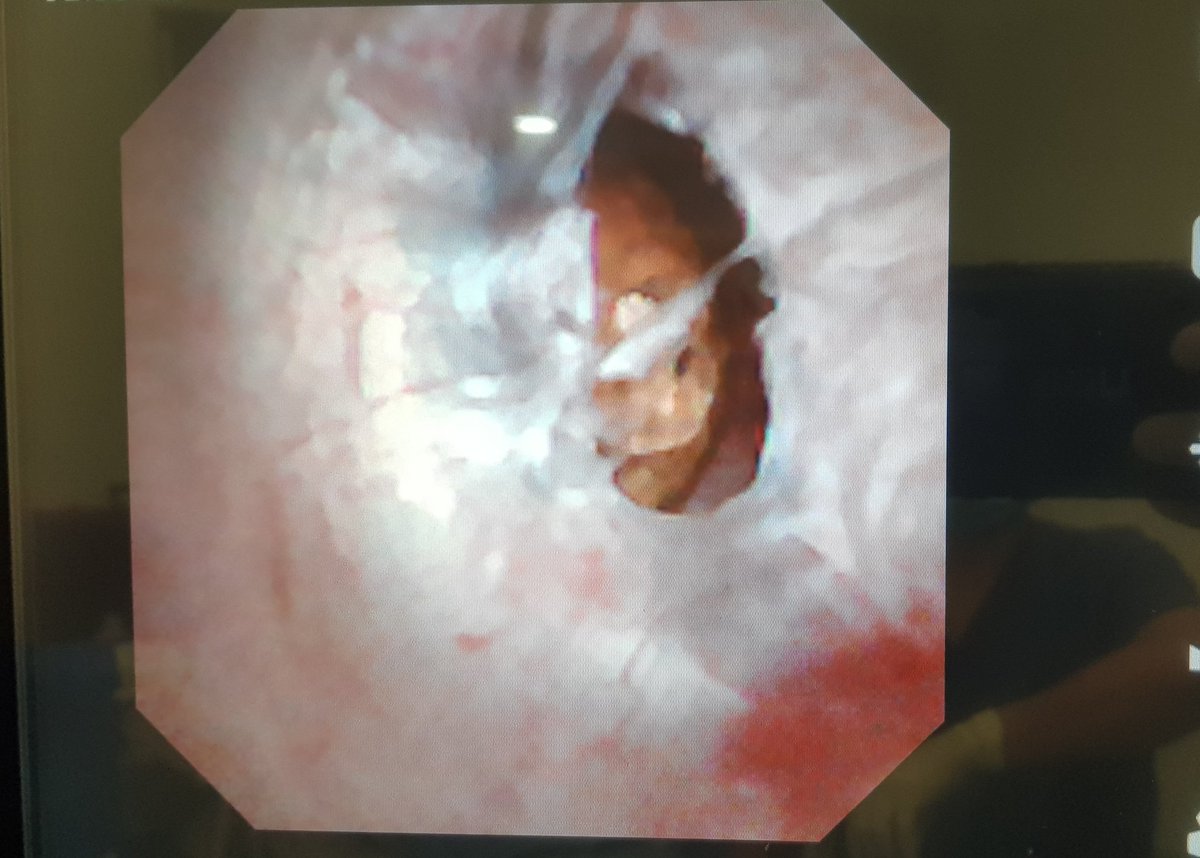

Enucleacion de

#Mioma uterino por#Histeroscopia con láser de#Holmium por el Dr. Jose Alanis en el@hospitalangeles del Carmen en el curso de Cirugía de Mínima invasión y Puerto Único#Guadalajarapic.twitter.com/A1oONbII9q -